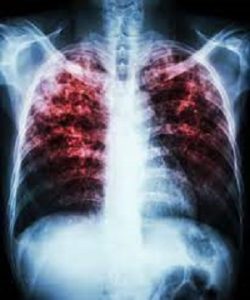

इंदौर। टीबी (TB) की बीमारी के इलाज के लिए की गई मेडिकल जांचों (medical examinations) के दौरान खुलासा हुआ कि इंदौर जिले में 250 से ज्यादा ऐसे मरीज हैं, जो दो-दो जानलेवा बीमारियों से दोहरी जंग लड़ रहे हैं। किसी को टीबी की बीमारी थी तो वो कुछ दिनों बाद एड्स (AIDS) की या फिर कोई एड्स (AIDS) से पीडि़त था तो टीबी (TB) के चपेट में आ चुका है ।

जिनको एमडीआर टीबी प्लस एड्स हो जाता है, ऐसे मरीजों को कई शारीरिक समस्याओं का सामना करना पड़ता है। इस दौरान इन मरीजों के फेफड़े, पेट, रीढ़ की हड्डियों सहित आंतों में पानी भर जाता है। फेफड़े और आंतें गलने लगती हैं। बदन का वजन लगातार कम होने लगता है, भूख नहीं लगती है।